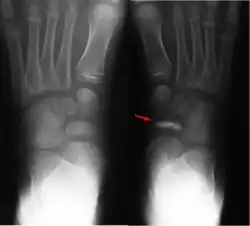

Im Röntgenbild imponieren eine scheibenförmige Verschmälerung und eine zunehmende Knochendichte im Os naviculare. Ein schollenförmiger Zerfall des Knochens ist möglich. Weiterhin besteht eine Gelenkspaltverbreiterung zwischen Talus und Os naviculare.